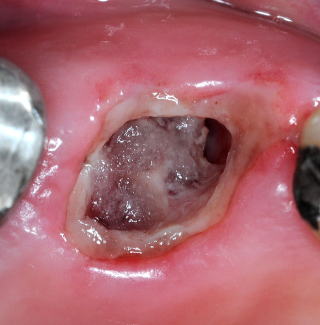

(図6)左上7抜歯直後。根尖部まで照明が届く同軸照明。内視鏡による術後処置で、Dry socketを完全に防止できる